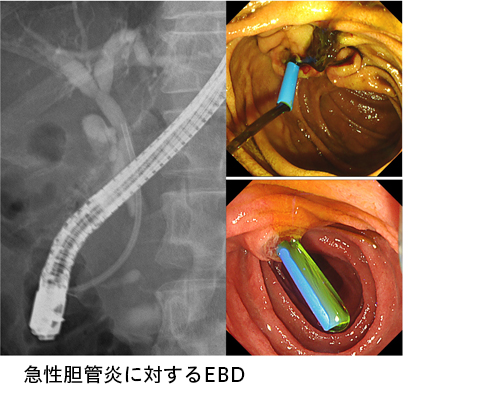

【タイムセール!】 胆膵内視鏡の診断・治療の基本手技 |本 隆夫 糸井 | 第3版 健康・医学の詳細情報

胆膵内視鏡の診断・治療の基本手技 第3版 | 糸井 隆夫 |本。胆膵内視鏡 診断・治療の基本手技 第4版 | 糸井 隆夫 |本 | 通販。胆膵内視鏡の診断・治療の基本手技 第3版 | 糸井 隆夫 |本。国産米粉のホットケーキミックス☆驚くほどもっちり☆MOLINAGA☆2袋セット。胆膵内視鏡 診断・治療の基本手技 第4版 - 羊土社。最先端治療 胆道がん・膵臓がん – 法研。裁断済(バラバラ)の本です。胆膵内視鏡の診断・治療の基本手技 第3版 - 羊土社。。胆膵内視鏡 診断・治療の基本手技 第4版 - 羊土社。胆膵内視鏡でサポートバンドを導入 - 事例紹介|Medicle。内視鏡センター|社会医療法人三栄会 ツカザキ病院。胆膵内視鏡の診断・治療の基本手技 改訂2版」付録DVD。胆膵内視鏡の診断・治療の基本手技 - 羊土社。裁断済みの為、状態が悪いとしていますが、書き込み等ございません。使い方の分かる方のご購入をお願いいたします。JDDWで売上1位を獲得した話題の新刊『これで完璧!胆膵内視鏡の